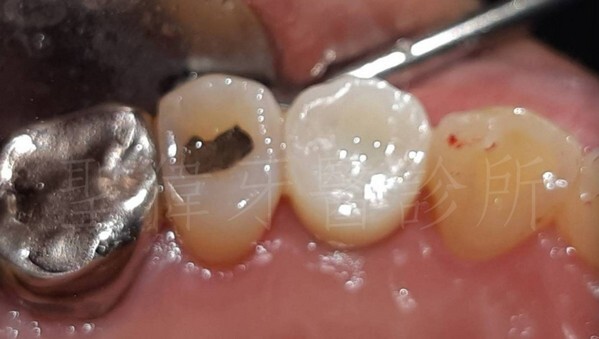

▼植牙後的照片

小臼齒正式歸位,看起根本真牙的狀態

大小、形狀、咬合,都非常的自然阿